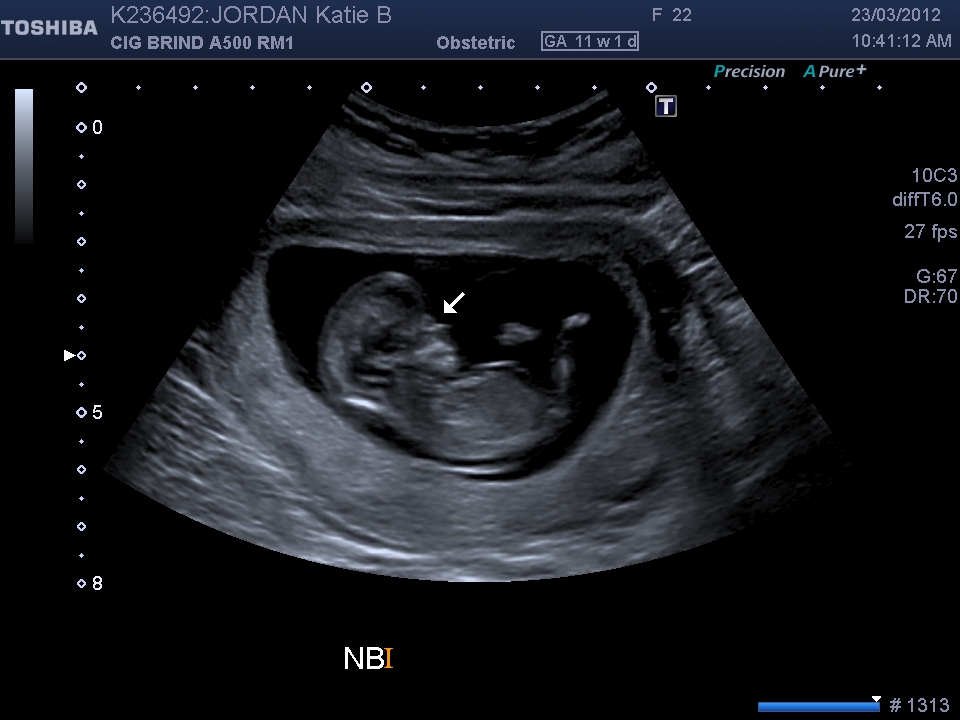

11w 1d is a bit early.

Based on a scull, I'd say :XX:

11 weeks is a bit early, potty shots unreliable and sorry but i cant see a nub in the profile shot. Do you have any other pics?

Lean :DD: guess, the shot's not that great for me to see nub but the skull looks girly to me.

Girl lean based on skull.